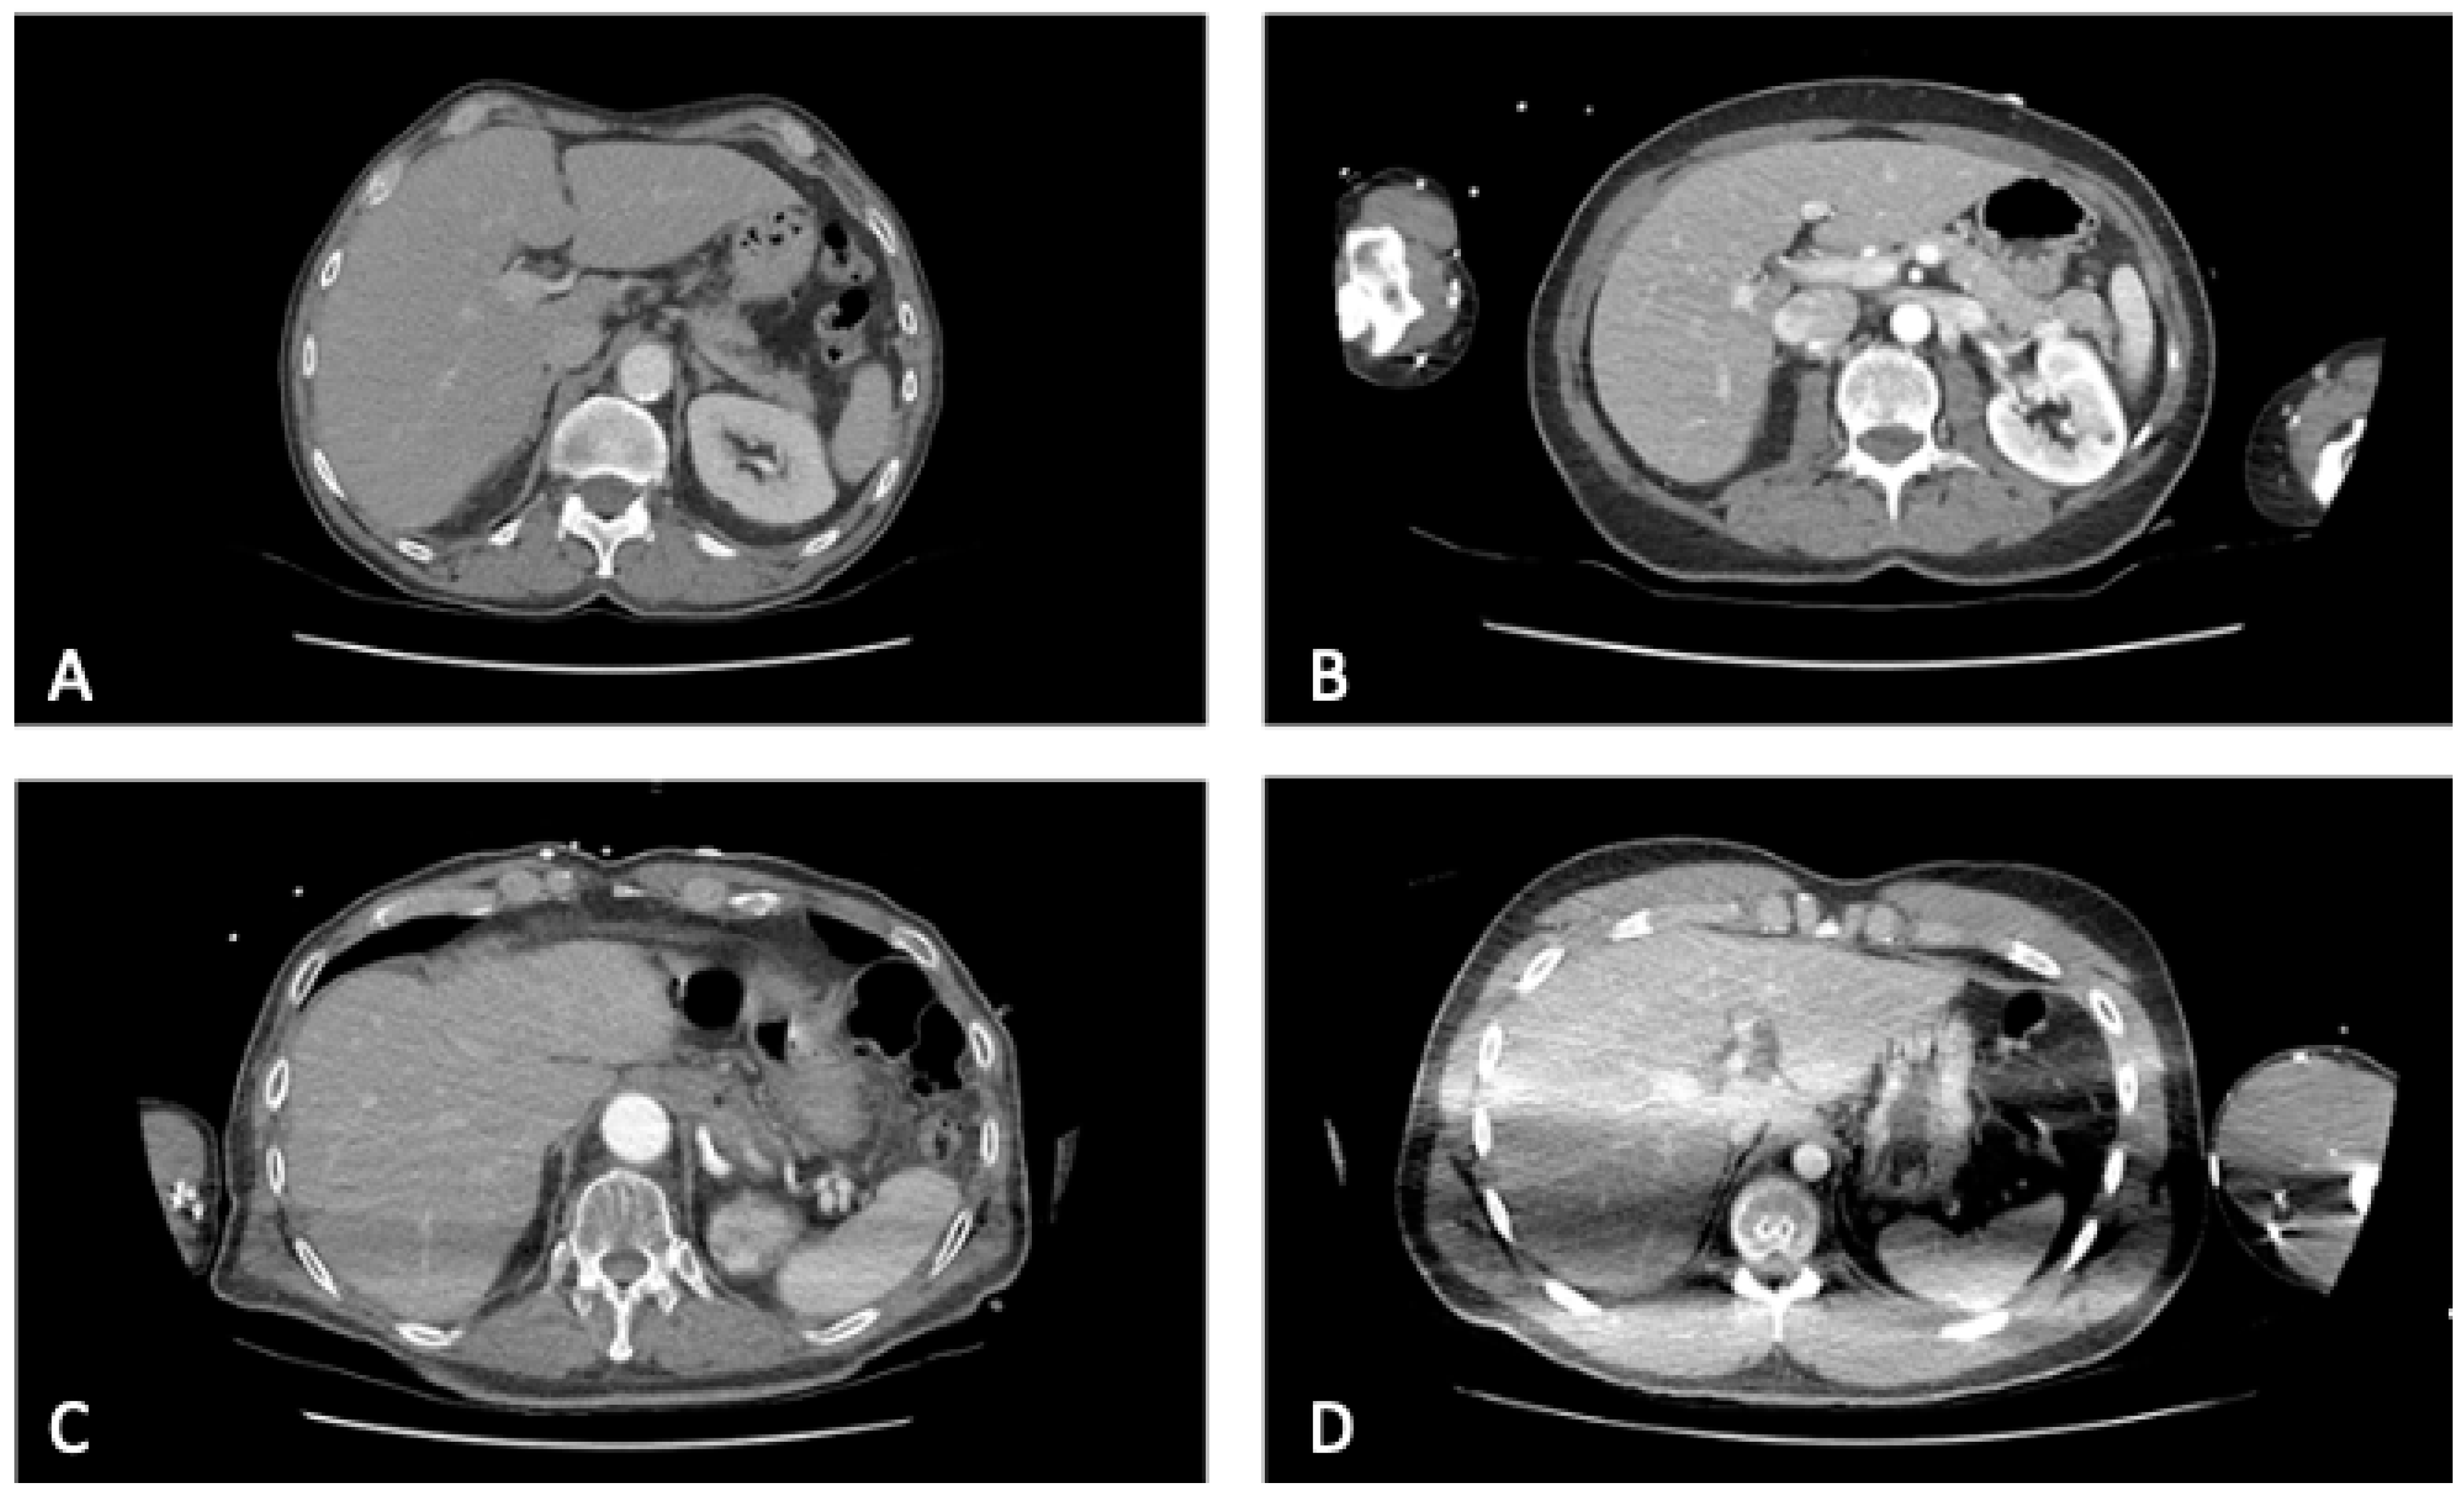

| Artifacts mean ± SD | 2.6 ± 0.9 | 1.0 ± 0 | 1.0 ± 0 | <0.001 | <0.001 |